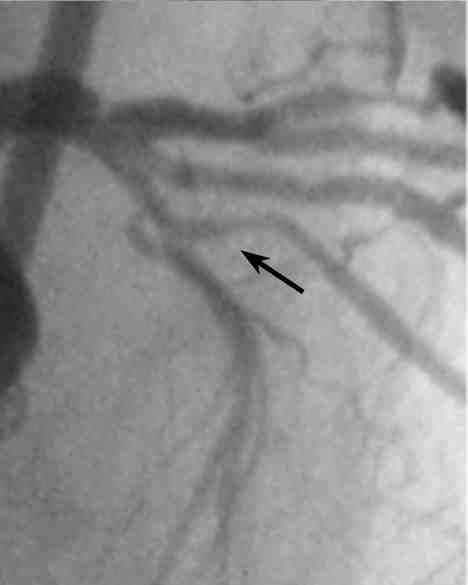

Figure 2: Patient with Chronic Total Occlusion in proximal LAD

This CTO is located immediately after the bifurcation of the diagonal, and though

it is unclear how long it has been occluded, the patients medical history suggests

that it may be a number of years. CAG does not clearly identify the CTO ostium,

(white arrows show an area that looks like the entry but black arrows show an

actual dimple). It is only by the AP cranial view that the dimple be seen at

all, and that only when viewed by frame by frame slow motion. This could easily

be missed under normal CAG.